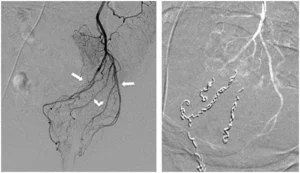

Intervenire precocemente è fondamentale per evitare il peggioramento della patologia. I trattamenti attuali, soprattutto nelle fasi iniziali, permettono di risolvere il problema con procedure minimamente invasive, che garantiscono un recupero rapido e con minimo dolore. Tecniche innovative come la radiologia interventistica offrono soluzioni avanzate per il trattamento delle emorroidi resistenti ai rimedi tradizionali, riducendo il rischio di recidive e migliorando la qualità della vita dei pazienti.